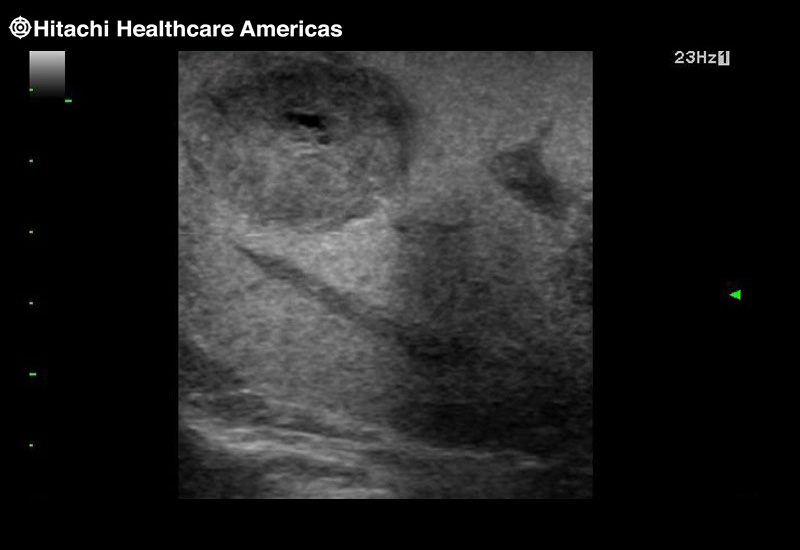

Superior guidance for all applications

Fujifilm Healthcare Americas is committed to designing tools that help surgeons navigate inside the human body and provide the necessary information to immediately make critical surgical decisions.

Fujifilm Healthcare's dedication to Surgeons provides outstanding ultrasound technology, professional support and the specialized tools necessary to best perform comprehensive real-time ultrasound imaging in Breast Surgery, General Surgery, Laparoscopic Surgery, Neurosurgery, Robotic Surgery and Surgical Oncology.

Imaging Clearly Defined

State-of-the-art digital architecture and advanced imaging features to redefine the capabilities of surgical ultrasound.